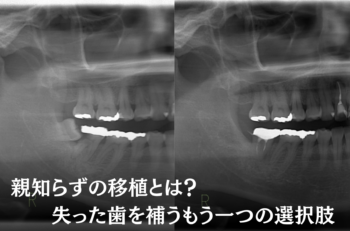

自家歯牙移植(親知らずの移植)って知ってますか?

実はそのほかに、『親知らずを利用して失った歯を補う』という治療法があるのをご存じですか?

それが『親知らずの移植(歯牙移植)』です。今回は親知らずの移植について、メリット・デメリット、治療の流れ、成功率、費用、そしてよくある質問までわかりやすく解説します。

親知らずの移植(歯牙移植)とは?

例えば、むし歯や歯周病で歯を失った場合、そのままにしておくと噛み合わせや歯並びに影響が出てしまいます。そんなとき、親知らずが健康な状態で残っていれば、それを抜いて失った場所に植え替えることが可能です。